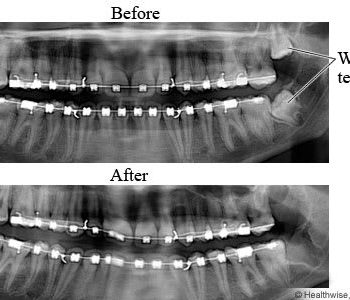

X-rays and evaluation to determine the best treatment approach.